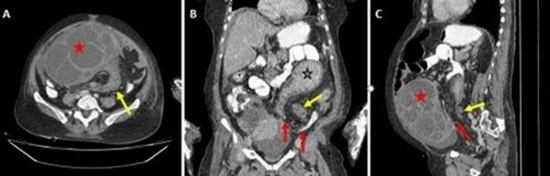

Sigmoid volvulus in a postmenopausal woman with ovarian cyst torsion: A rare case report with review of literature

Background: Large bowel obstruction in adults may result from either mechanical or non-mechanical causes, with sigmoid volvulus (SV) being one of the most common mechanical etiologies. Concurrent SV and ovarian cyst torsion (OCT) is an extremely rare occurrence, particularly in postmenopausal women.

Case description: We present the case of a 50-year-old postmenopausal woman who initially presented with symptoms of colonic obstruction. Further evaluation revealed SV in conjunction with a large ovarian mass with torsion. The patient underwent unilateral salpingo-oophorectomy, subtotal colectomy, and end colostomy. Postoperative histopathological analysis confirmed a benign ovarian lesion.

Clinical discussion: SV is associated with high morbidity and mortality but may be managed conservatively with endoscopic detorsion in the absence of hemodynamic instability or signs of colonic ischemia or perforation. However, when an unresolvable mechanical trigger such as a large ovarian mass is present, surgical intervention remains the mainstay of treatment. To the best of our knowledge, this is the first reported case of obstructing SV occurring concurrently with OCT in a postmenopausal woman.

Conclusion: OCT should always be considered in the differential diagnosis for female patients of any age presenting with clinical features suggestive of small or large bowel volvulus